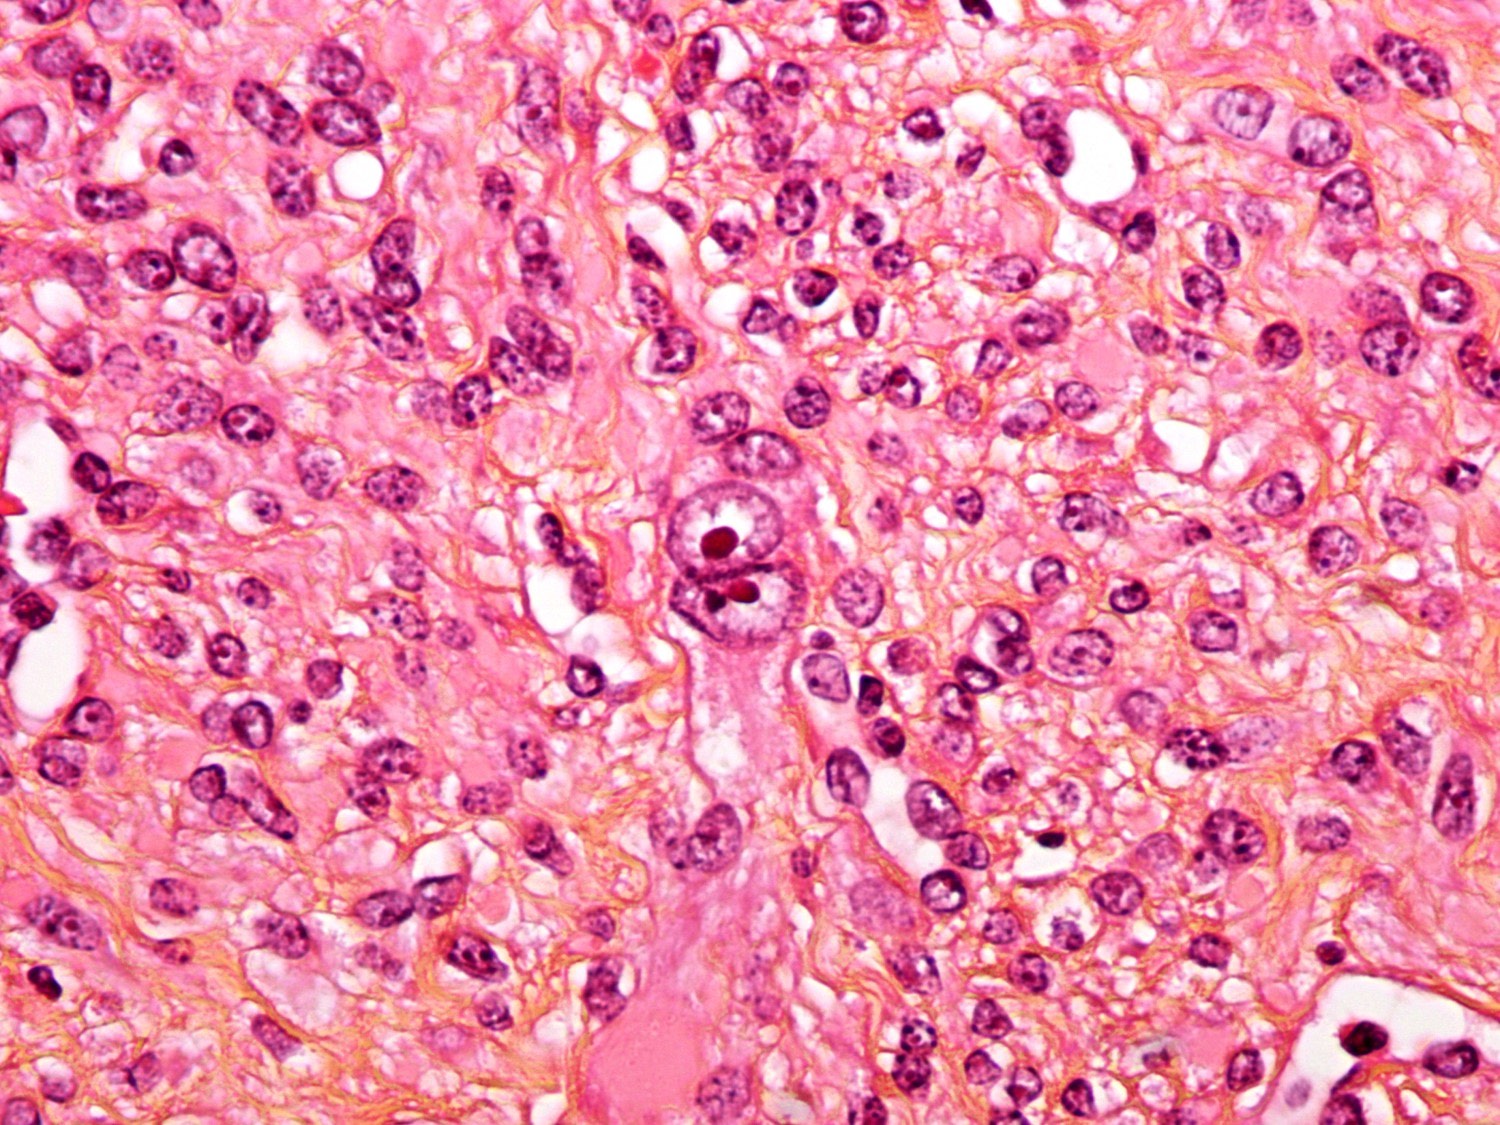

Microscopic (histologic) images

Contributed by Sabrina Croce, M.D., Ph.D., Kristina Doytcheva, M.D., Jennifer A. Bennett, M.D. (Case #508) and @Andrew_Fltv on Twitter

- Epithelioid:

- Round or polygonal cells with eosinophilic or clear cytoplasm (in general, ≥ 50% of tumor cells)

- Nested or trabecular architecture

- No cytologic atypia or tumor cell necrosis

- Mitotic count is < 2 mitoses/10 high power fields